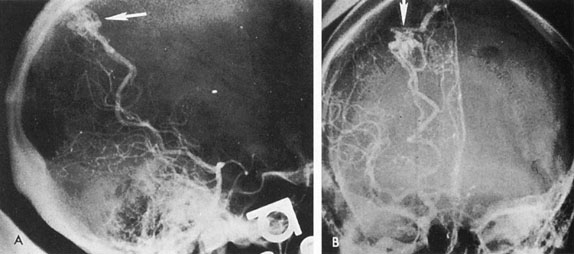

The therapy for AVMs has been reviewed elsewhere.91–93 The preferred treatment remains complete surgical excision of the malformation. However, significant advances in endovascular and radiosurgical techniques have resulted in a marked increase in the use of multimodal, staged approaches to AVM treatment. A variety of intravascular techniques use embolization91 with materials such as particles of polyvinyl alcohol (PVA), platinum coils, and injection of liquid N-butyl-cyanoacrylate (NBCA) adhesive (Fig. 11). Complications of intravascular embolotherapy include vessel perforation by the catheter, migration of embolic materials, and infarction and hemorrhage of normal brain.

Fig. 11. Embolization of middle cerebral vessels that supply occipital lobe arteriovenous malformation (AVM). The patient had a subarachnoid and intraparenchymal hemorrhage that produced a left homonymous field defect. A: Right carotid arteriogram demonstrates contribution via posterior communicating artery to a right occipital lobe AVM. B: Vertebral injection. The arrow points to the enlarged right posterior cerebral artery that is a major feeder of the AVM. C: Right carotid arteriogram during glue embolization procedure. The arrow points to a catheter as it traverses the segment seen in (B). The catheter was advanced via the internal carotid artery but is positioned far posteriorly. D: Upper branches to the AVM now are occluded, with residual low-flow vascularization via the middle cerebral artery. E: Skull film showing radiopaque glue within the AVM and blood vessels previously supplying it. The patient had a persistent visual field defect but greatly reduced headache and no persistence of subjective bruit. (Courtesy of Dr. Joseph Horton.)

Mechanisms of delivery of radiation therapy to AVMs include those of the linear accelerator (LINAC), gamma knife, and heavy charged particle beam (proton and helium ion Bragg-peak radiosurgery). Stereotactic radiosurgery is most commonly administered by gamma knife for a variety of intracranial disorders to include tumors and vascular malformations.94 Pollock et al61 believe that stereotactic radiosurgery is 80% effective for AVMs less than 3 cm in average diameter, within a latency period of 2 to 3 years, but the patient is at risk during the interval until obliteration of the lesion.